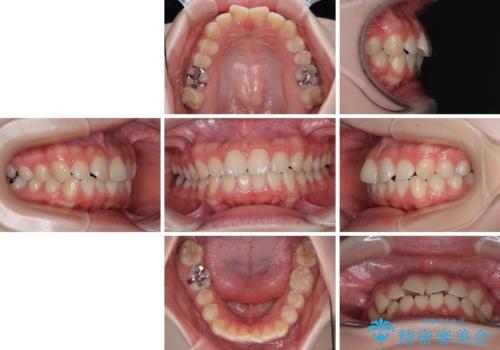

- 上下前歯部のデコボコを気にして来院された患者様です。

叢生は軽度であったため、マウスピースでもワイヤー装置でも対応可能でしたが、マウスピースを長時間使用する自信がないとのことでワイヤー装置にて矯正治療を行うこととしました。

叢生が軽度であったため、僅か半年で装置を除去することができました。